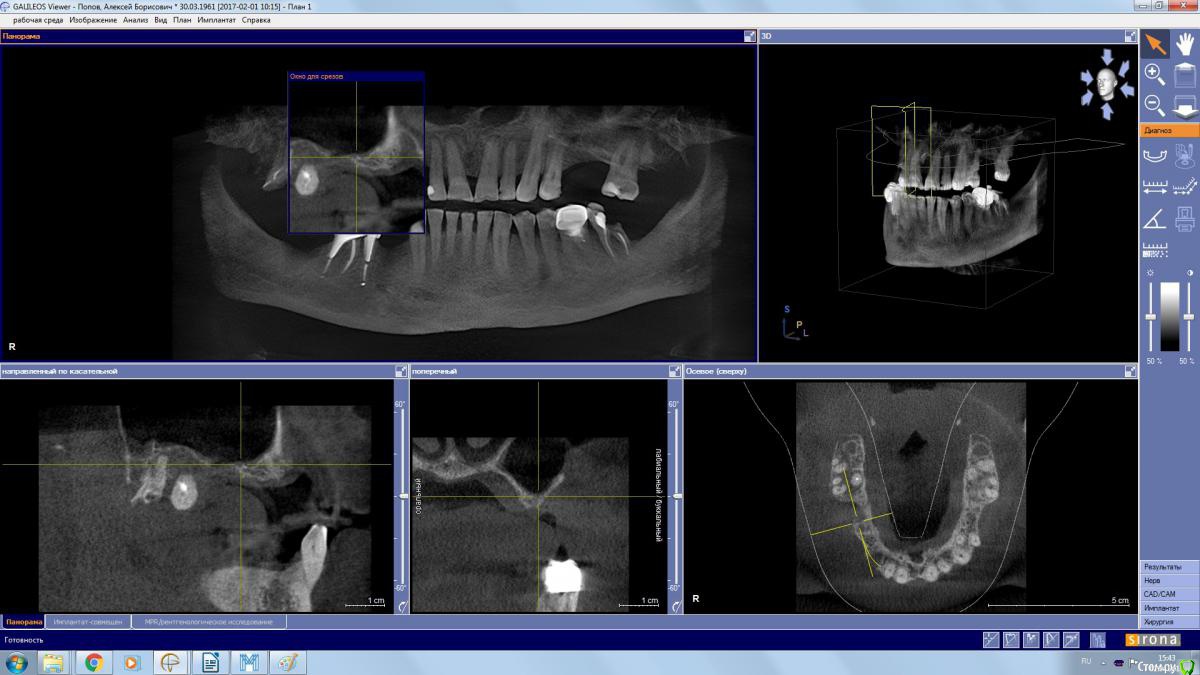

kamranchick Опубликовано 2 апреля, 2017 Автор Поделиться Опубликовано 2 апреля, 2017 Да дыры какие то и на окклюзионной поверхности и сбоку) это и отпугнуло Ссылка на комментарий

колесников Опубликовано 2 апреля, 2017 Поделиться Опубликовано 2 апреля, 2017 Дыру закрыть можно, главное из дыры отслоится без разрывов. Рубцовска ткать прочно врастает в края дефекта,я бором прохожусь по контуру дефекта и отделяю рубцовую заплатку вместе со шнейдоровой относительно легко. Ссылка на комментарий